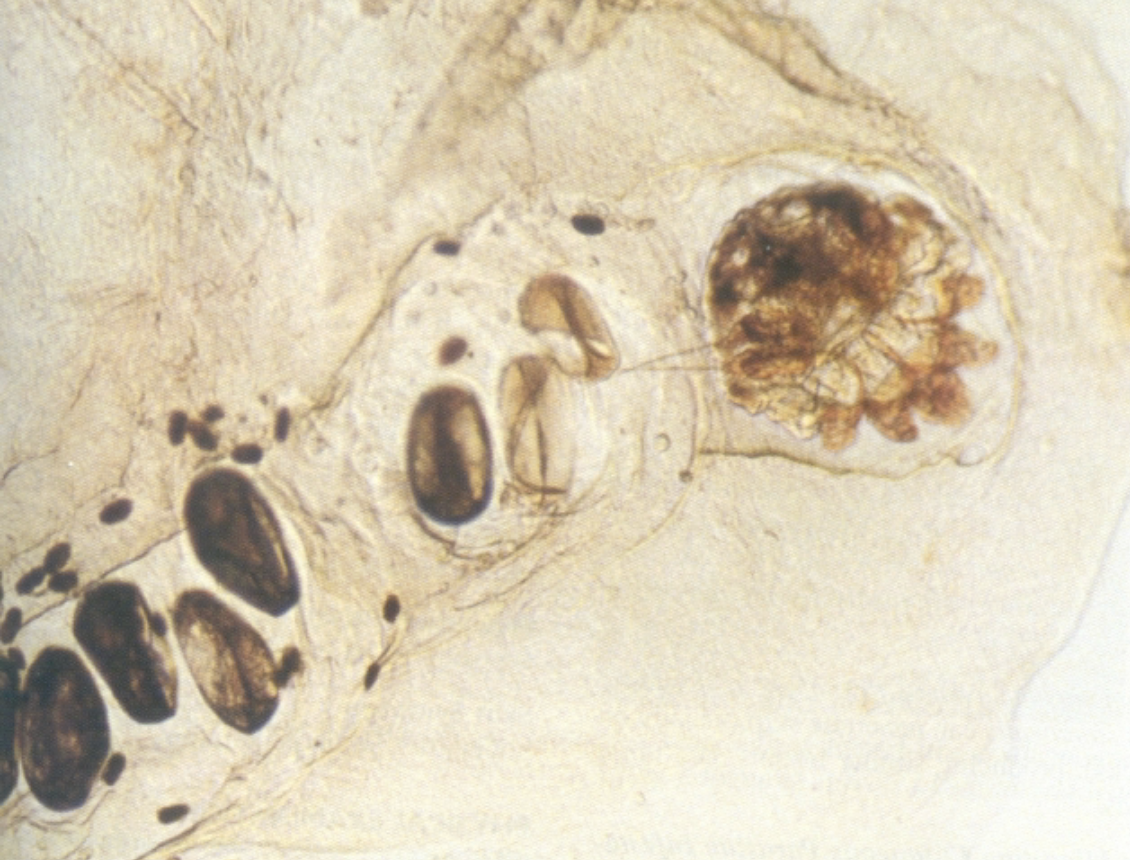

Sarcoptes scabiei tunneling

Ova and fecal pellets of Sarcoptes scabiei